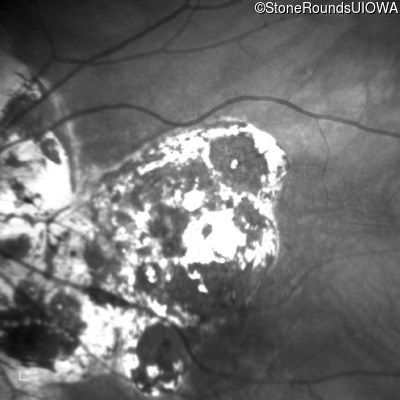

Blue Autofluorescence - Right - 20/160 -2

Exemplar